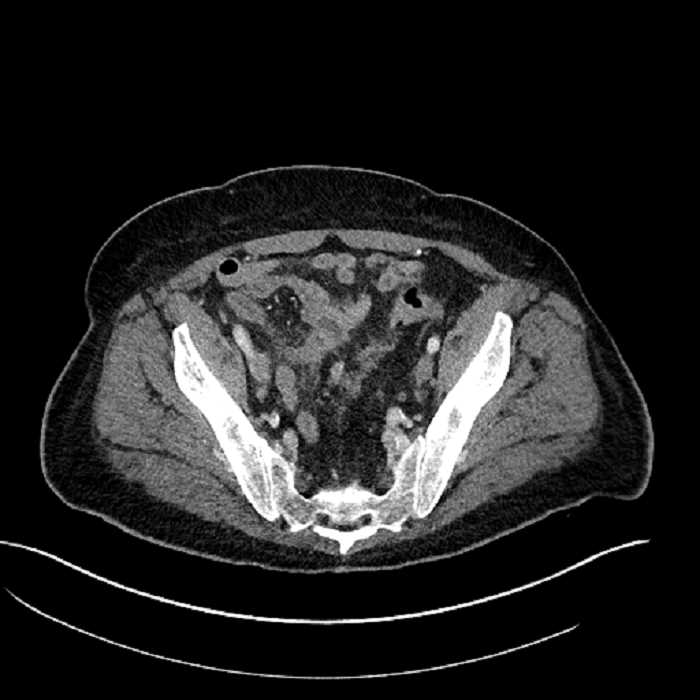

• Mild mural thickening of a segment of the sigmoid colon with adjacent fat stranding and a 1.5 cm fluid and gas collection along the tip of an inflamed diverticulum

• Loss of the normal fat plane between this collection and adjacent loops of small bowel, which demonstrate mural thickening

• High grade stenosis of the left common iliac artery, with the left internal and external iliac arteries remaining patent

Acute sigmoid diverticulitis complicated by a small contained perforation and a large abscess in the right hepatic lobe. Additional small subcapsular abscesses along the anterior margin of the left hepatic lobe.

Additionally, loss of the normal fat plane between the peridiverticular collection and adjacent thickened loops of small bowel raises the potential for an enterocolonic fistula.

High grade stenosis of the left common iliac artery. The left external and internal iliac arteries are patent.

Hepatic abscess showing the double target sign with low density internally surrounded by a thin inner enhancing rim (red arrow) and ill-defined outer low density rim (yellow arrow). Blue arrow indicates an internal septation. Red arrows: additional smaller subcapsular abscesses. Red arrow: focal contained perforation associated with diverticulitis.